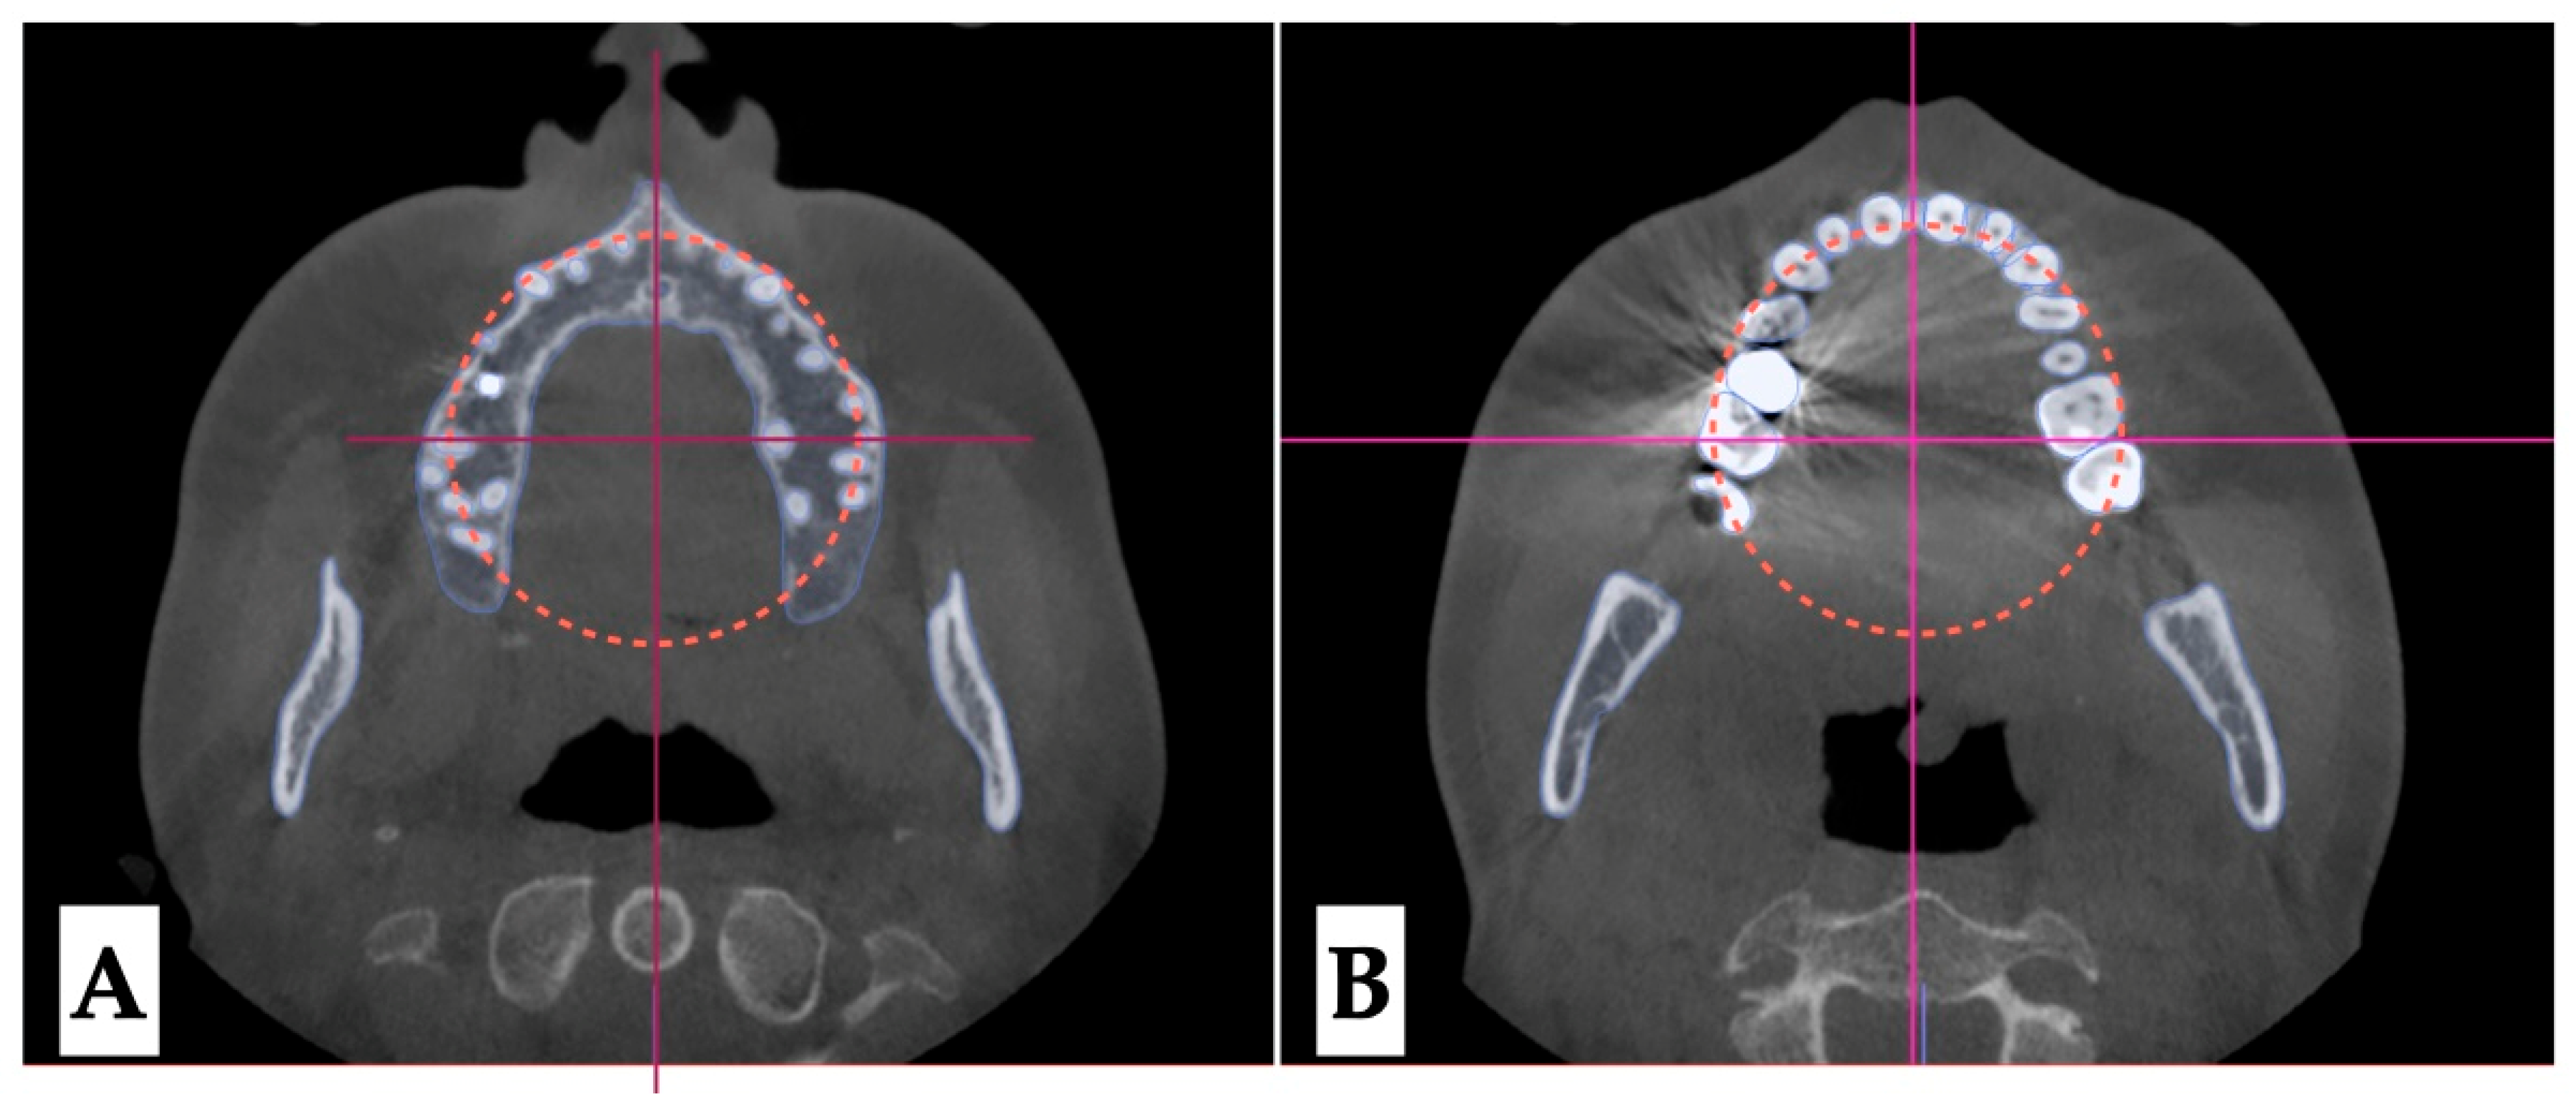

2.3.2. Design of 3D Surgical Guide

2.3.3. Osteotomy Planning and Appliance Design

2.3.4. Postoperative Assessment, Outcome Analysis, and Asymmetry Correction